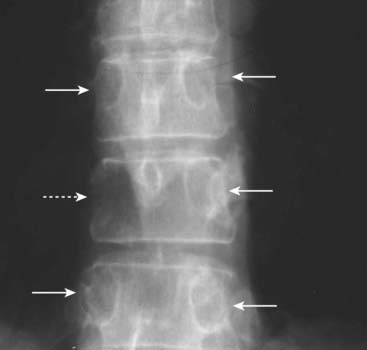

imagePaget disease is usually diagnosed using conventional radiography. The imaging hallmarks of Paget disease:

image Thickening of the cortex. To recognize thickening of the cortex, compare the thickness of the cortex of the suspicious area with another part of the same bone or, if visible, the same bone on the opposite side of the body.

image Accentuation of the trabecular pattern. There is coarsening and thickening of the trabeculae (Fig. 21-12).

image Increase in the size of the bone involved. The “classical” history for Paget disease, rendered less useful as fashions have changed, was a gradual increase in a man’s hat size as the calvarium increased in size from this disease.

image

Figure 21-12 Paget disease of the pelvis, two patients.

A, A frontal view of the pelvis shows an increase in bony density in the left hemipelvis, accentuation and coarsening of the trabeculae, and thickening of the cortex (white circle), the hallmarks of Paget disease of bone. Compare the left hemipelvis with the normal right side. B, Axial CT scan of the pelvis of another patient with Paget disease demonstrates thickening of the cortex and accentuation of the trabeculae in the right ilium (solid white arrow). Compare it with the normal left side (dotted white arrow).